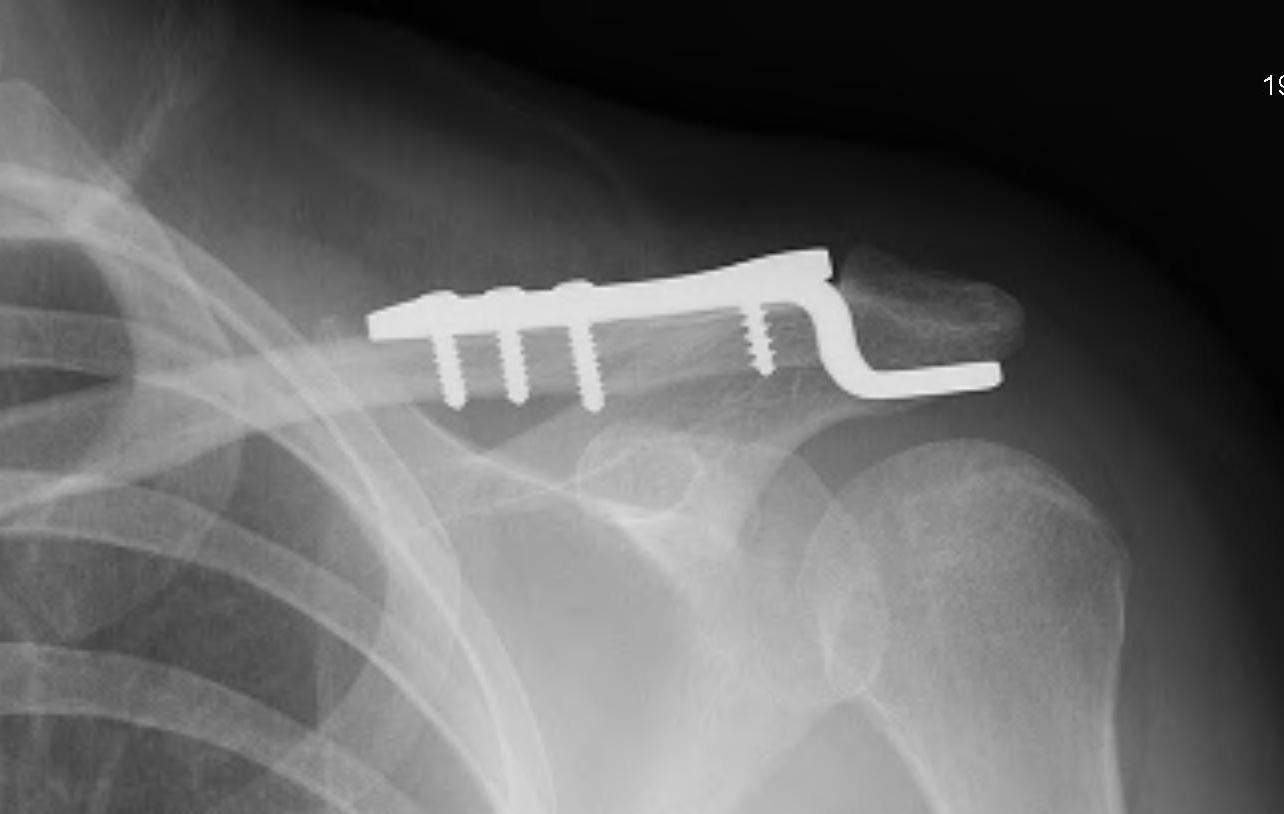

Hook plate

Technique

Reduction of ACJ

- hook under posterior acromion

- allows CC ligaments to heal

- need to remove plate at 4 - 6 months

Risks

Subacromial erosion - may be reduced by increasing the angle on the hook

Hook plate cut out through acromion - need to remove hook plate at 6 - 8 weeks

Clavicle fracture at end of plate